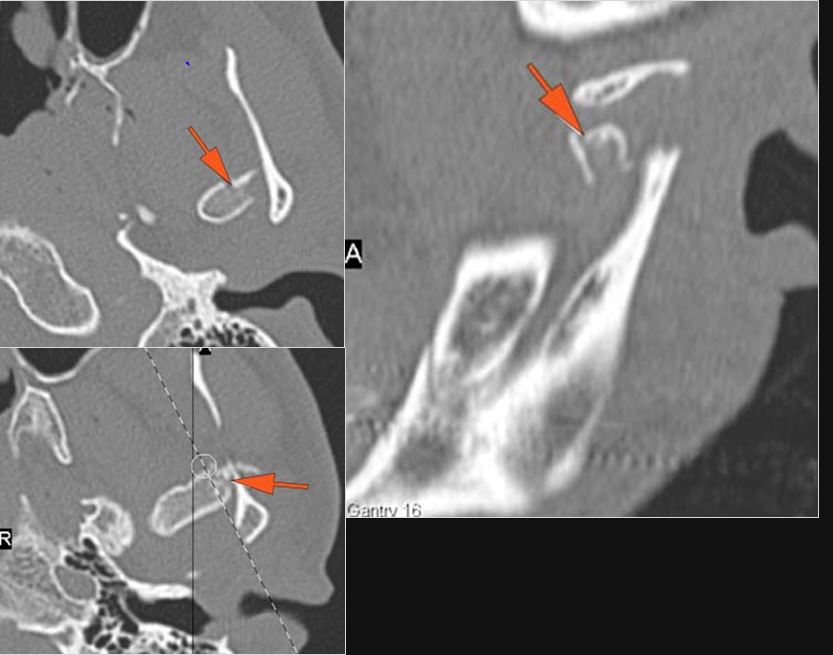

Mandible and Temporomandibular Joints

There is condylar fracture either within or outside of the joint capsule, or with or without involvement of the articular surface of the condylar head.

There is bony injury or displacement of the external auditory canal and/or other evidence of temporal bone injury.